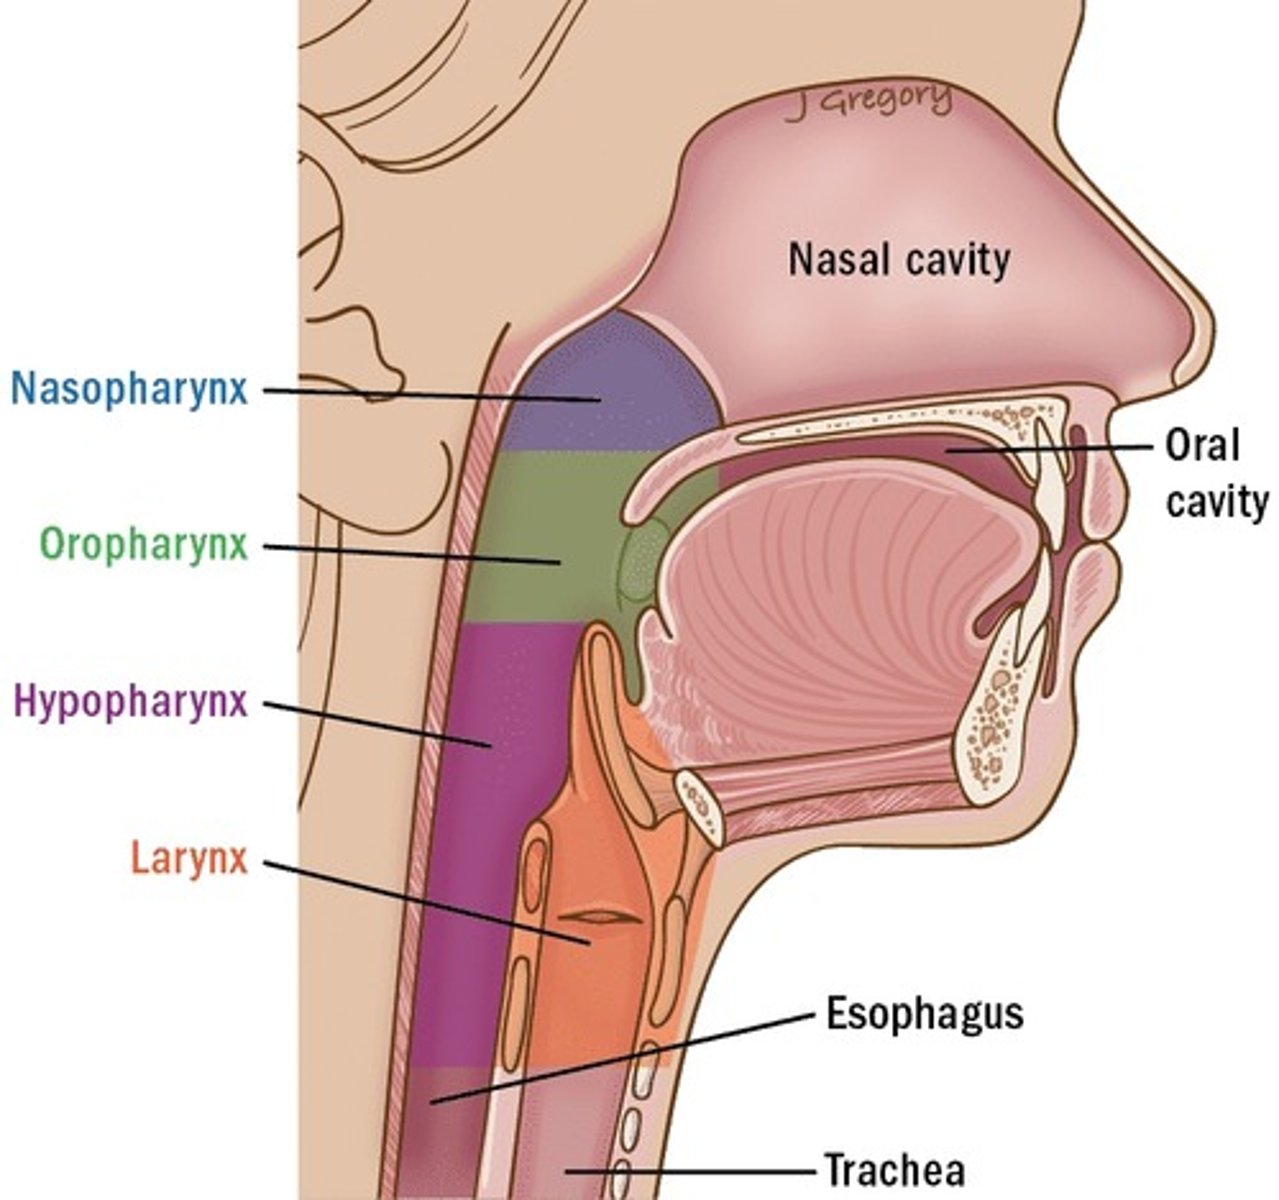

What structures make up the extrapulmonary respiratory tract?

Nasal cavity, pharynx, larynx, trachea, and primary bronchi.

What is Waldeyer's ring?

A ring of lymphoid tissue surrounding openings into digestive and respiratory tracts.

What structures are included in Waldeyer's ring?

Pharyngeal (adenoid), tubal, palatine, lingual tonsils, and diffuse lymphatic tissue.

Where is the larynx located?

Between the oropharynx and trachea.

What epithelial transition occurs in the larynx?

Understand how the epithelium changes from epiglottis to treachea`

Epiglottis - stratified squamous epithelium with elastic cartilage

False vocal cords - pseudostra. cillated epithelium

True vocal cords - stratified sq. non keratinized epithelium with skeletal muscle

Trachea - pseudostra. ciliated epithelium with goblet cells (respiratory structure)

Larynx (voice box)

Identify the entire structure